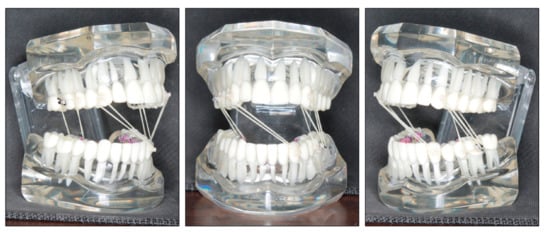

- Extraction of upper third molars, lower right first molar and left second molar would be performed. With this approach, the upper lip would not be retracted, and molar Class I relationship could be achieved. The rationale of asymmetric molar extraction was that mandibular right first molar extraction would provide more strong posterior molar anchorage to correct midline deviation and canine Class III relationship on the right side;

2.4. Treatment Plan